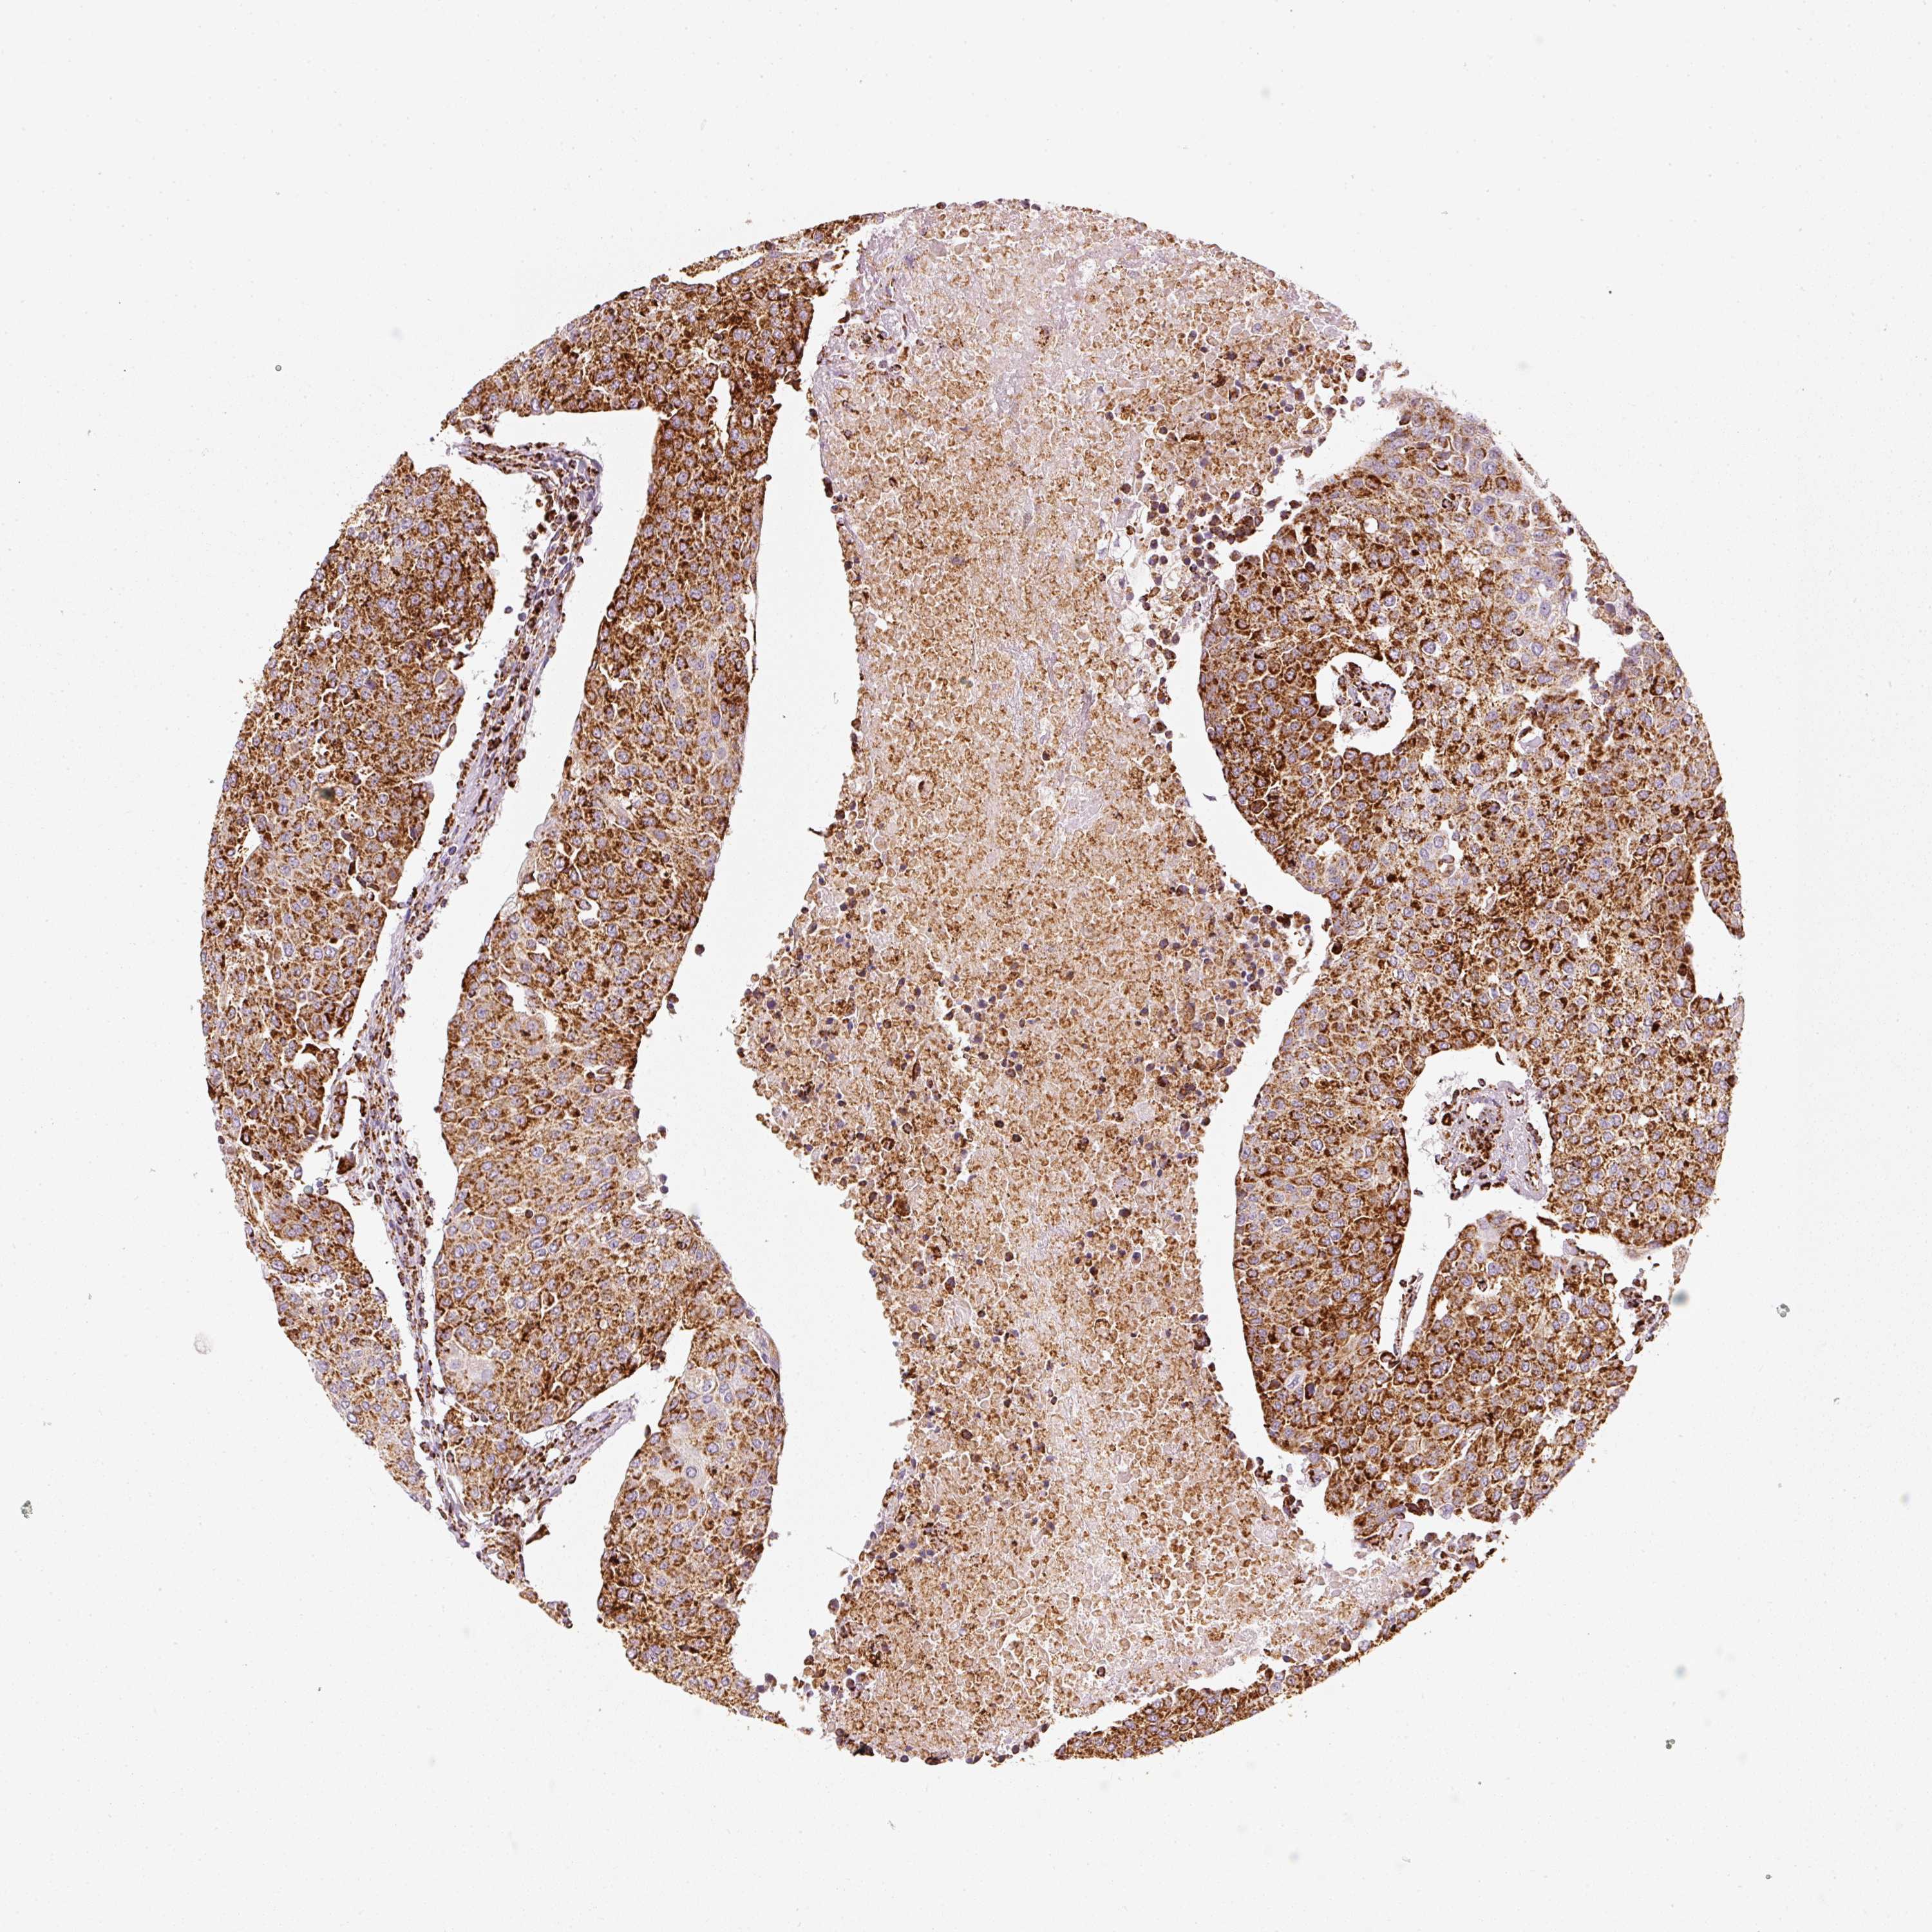

UROTHELIAL CANCER - Protein expressioni

A mouse-over function shows sample information and annotation data. Click on an image to view it in a full screen mode. Samples can be filtered based on level of antibody staining by selecting one or several of the following categories: high, medium, low and not detected. The assay and annotation is described here.

Note that samples used for immunohistochemistry by the Human Protein Atlas do not correspond to samples in the TCGA dataset.

Antibody stainingi

Antibody staining in the annotated cell types in the current human tissue is reported as not detected, low, medium, or high, based on conventional immunohistochemistry profiling in selected tissues. This score is based on the combination of the staining intensity and fraction of stained cells.

Each image is clickable and will lead to virtual microscopy that enables deeper exploration of all samples and also displays staining intensity scores, fraction scores and subcellular localization as well as patient and tissue information for each sample.

Antibody HPA051505

Antibody HPA054758

Antibody CAB016243

Staining

High

Medium

Low

Not detected

Intensity

Strong

Moderate

Weak

Negative

Quantity

>75%

75%-25%

<25%

None

Location

Nuclear

Cytoplasmic/membranous

Cytoplasmic/membranous,nuclear

Urothelial carcinoma, High grade

Urothelial carcinoma, Low grade